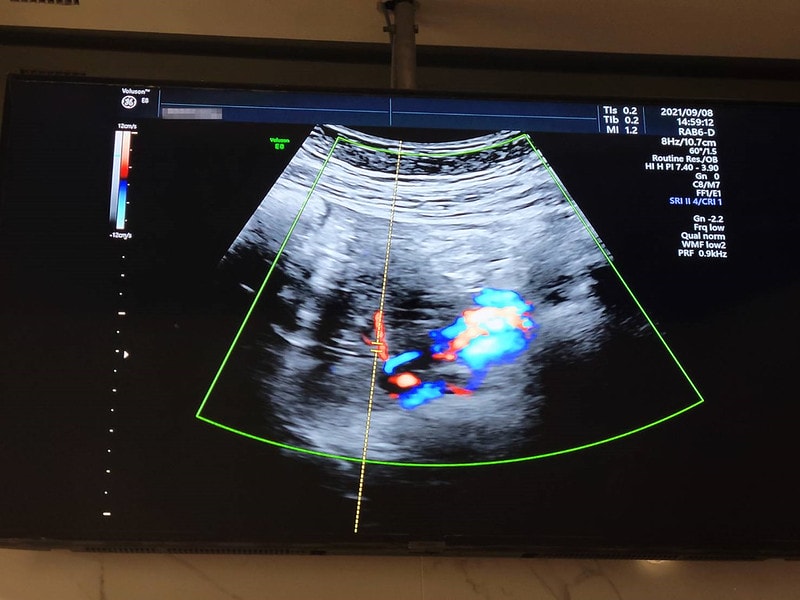

關於孕期出血

(很多孕婦 可能從懷孕到生中間都不會出血)

我自己出血大概是12周的時候遇到的

不知道是不是前一天活動量比較大的關係

檢查內褲發現有鮮血

而且不是淡淡的粉色

就真的是紅色的那種

嚇到馬上直奔婦產科診所

還問醫生說”醫生出血是正常的嗎?”

醫生回了我一句”當然不正常啊”

會開黃體素和安胎藥給你,就是乖乖吃

吃了兩天大概就沒大礙,之後也沒再遇到出血

總之不管是怎樣類型的出血

都不會是正常的

最好還是馬上去看醫生

至於為什麼會出血,有滿多種原因的

醫生是說我有胎盤位置過低的問題

加上和子宮頸中間有條縫隙

如果可能太累或摩擦到就會比較容易出血